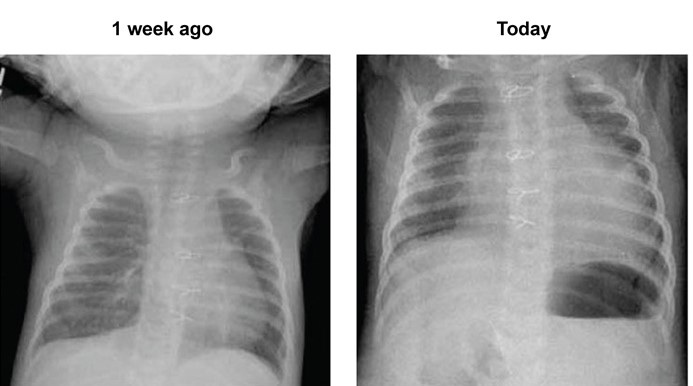

A 4-week-old male infant with hypoplastic left heart syndrome has had difficulty feeding and an episode of vomiting over the last 24 hours.  He was born at term via normal spontaneous vaginal delivery.  The patient underwent palliative heart surgery at age 1 week; the procedure involved cardiotomy and extensive intracardiac and aortic arch repair.  His postoperative course was uncomplicated, and he has remained in the hospital for weaning of oxygen and titration of cardiac medications.  Two additional palliative surgeries are planned.  Temperature is 38.3 C (101 F) , blood pressure is 80/40 mm Hg, pulse is 175/min, and respirations are 70/min.  Pulse oximetry is 80% on room air.  He is cyanotic and small for his age.  Cardiopulmonary examination is notable for distant heart sounds, tachycardia, and tachypnea.  Abdominal examination is normal.  Chest radiographs from a week ago and today are shown below. A 4-week-old male infant with hypoplastic left heart syndrome has had difficulty feeding and an episode of vomiting over the last 24 hours.  He was born at term via normal spontaneous vaginal delivery.  The patient underwent palliative heart surgery at age 1 week; the procedure involved cardiotomy and extensive intracardiac and aortic arch repair.  His postoperative course was uncomplicated, and he has remained in the hospital for weaning of oxygen and titration of cardiac medications.  Two additional palliative surgeries are planned.  Temperature is 38.3 C (101 F) , blood pressure is 80/40 mm Hg, pulse is 175/min, and respirations are 70/min.  Pulse oximetry is 80% on room air.  He is cyanotic and small for his age.  Cardiopulmonary examination is notable for distant heart sounds, tachycardia, and tachypnea.  Abdominal examination is normal.  Chest radiographs from a week ago and today are shown below.   Which of the following is the most likely cause of this patient's acute presentation? A) Congestive heart failure B) Endocarditis C) Mediastinitis D) Pericardial effusion E) Pulmonary embolism Which of the following is the most likely cause of this patient's acute presentation?